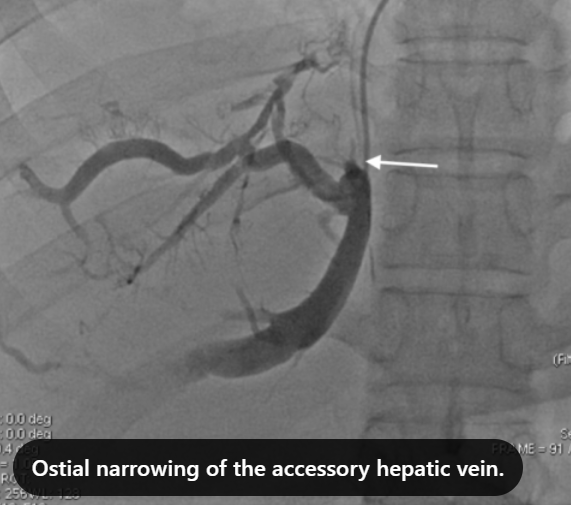

Clinical Case [Uncaptioned image] [Uncaptioned image]

Image Findings: The patient underwent contrast-enhanced computed tomography which showed features of a congested liver with flip-flop pattern of enhancement. Hepatic veins show hypoattenuation on delayed phase. An accessory hepatic vein is also noted in segment VI. A diagnosis of Budd Chiari syndrome (BCS) was made on the basis of the clinical and imaging features. The patient was referred to the interventional radiology team for an endovascular rescue. On conventional venogram, the diagnosis of BCS was confirmed as the hepatic veins were thrombosed. An accessory segment VI hepatic vein was noted draining into the IVC…